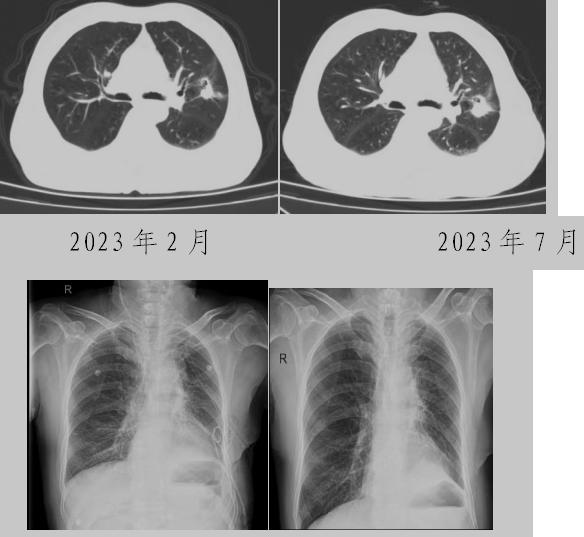

病例二:42歲的范女士,半年前體檢時發(fā)現(xiàn)雙側多發(fā)肺結節(jié),平時沒有什么不適。四個月后再次復查胸部CT,左上肺及下肺多發(fā)的磨玻璃結節(jié),其中下葉9mm的結節(jié)定為高危病灶。看到結果范女士坐不住了,多方打聽慕名找到了市二院院長王瑾,經(jīng)“肺結節(jié)MDT”團隊會診后,決定手術治療。入院后,胸外科副主任醫(yī)師薛飛詳細與范女士溝通,并利用Mimics做好了術前肺部三維重建手術規(guī)劃,打消了范女士心中的顧慮。經(jīng)過前期充分準備后,歷經(jīng)1小時30分,完成“胸腔鏡下左肺上葉舌段楔切及左肺下葉背段切除術”,術后病理檢查結果確診為左肺微浸潤性腺癌。在胸外科團隊的悉心照顧下,患者術后恢復良好,一周后順利出院。